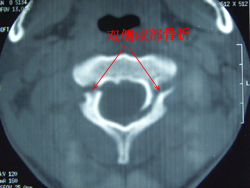

寰樞關節脫位這些患者並沒有經受很大的暴力傷,有些甚至沒有外傷史,只是因為頸痛就診攝了開口位X線片,見到齒狀突與兩側寰椎側塊不等距。有些病例CT橫截面上也見到兩側寰齒側間隙不等距。這些病例都經過了牽引及支具治療,均未能糾正“脫位”,個別病例甚至因此而做了寰樞關節融合術。對這些病例作出“寰樞關節脫位”的診斷是不恰當的。如果有齒狀突骨折,在頸椎側位片及開口位片上可以見到骨折線或骨折移位的影像。橫截面的CT可以觀察到寰椎橫韌帶的起止點是否有撕脫骨折。如果橫截面CT影像見寰樞關節鏇轉角度超過47度,即可診斷寰樞關節脫位。

寰樞關節脫位2、CT檢查:

可與寰椎椎弓骨折及上頸椎畸形等疾病相鑑別,特別在頸部有創傷史,有頸部疼痛,僵硬或固定體位。而x線未發現異常時,CT檢查有助於防止漏診。